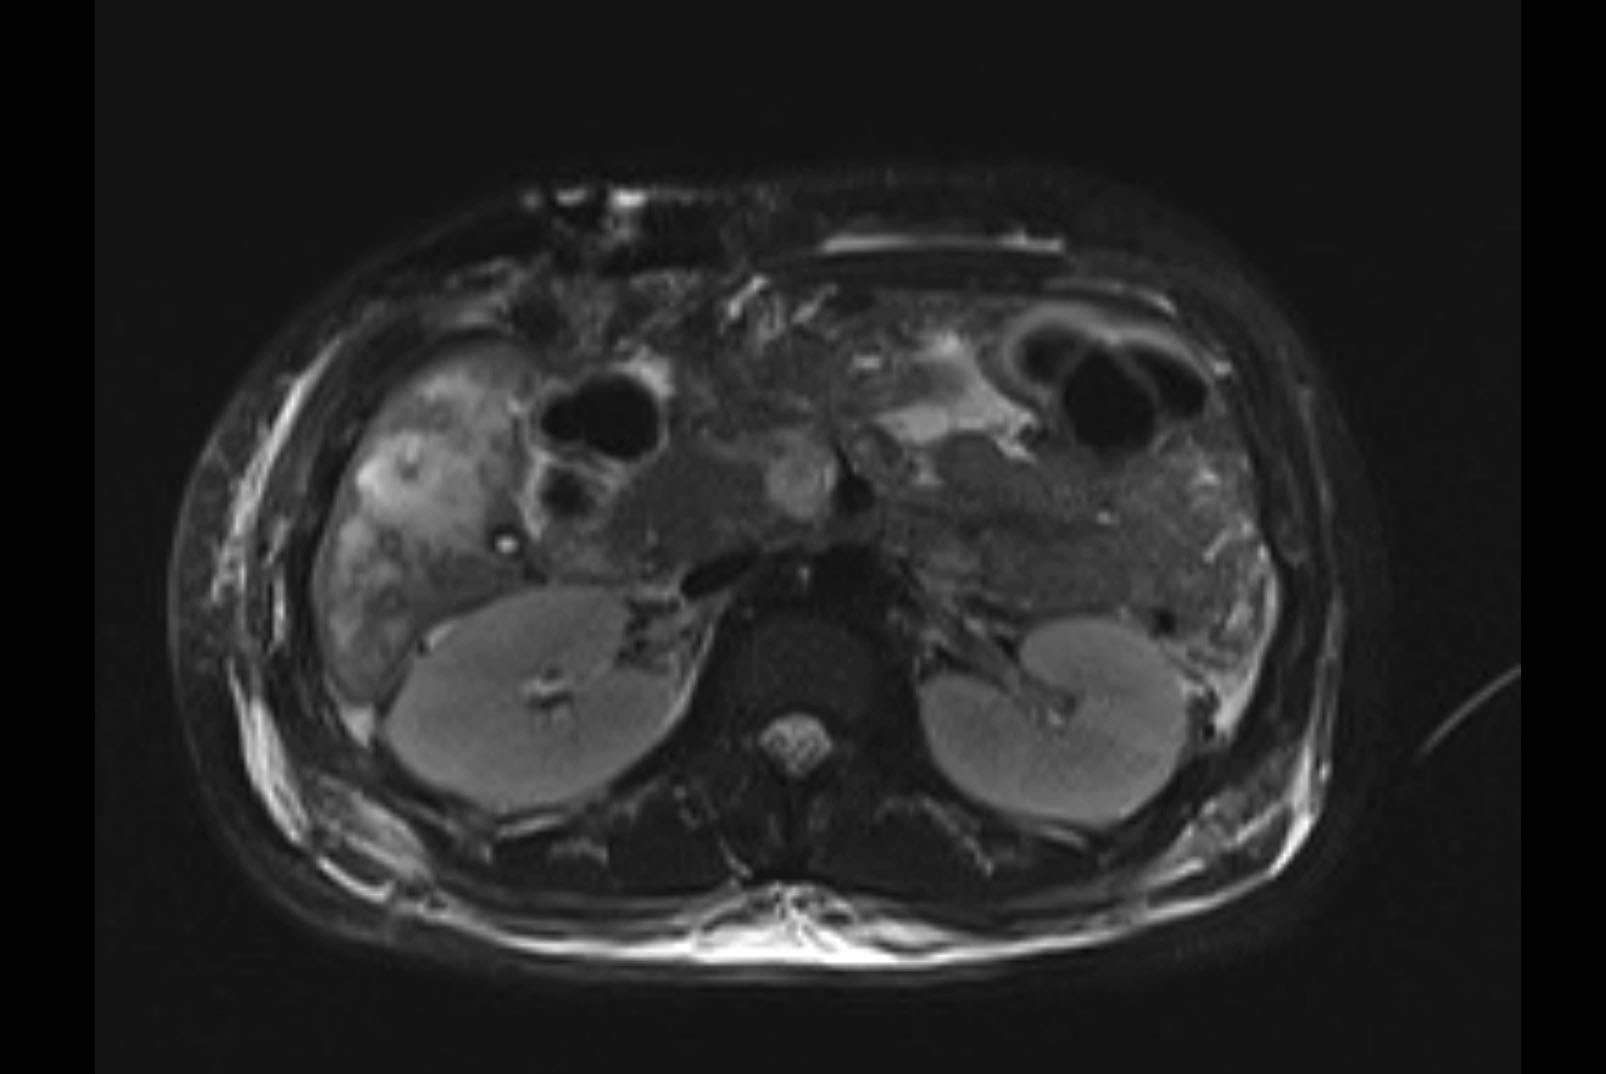

Imaging Analysis

Look through the patient's CT scan to identify any areas of concern for the necessary procedure.

MRI T1

MRI T2

Based on initial findings, which issue(s) would you be most concerned about?